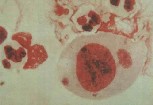

一、急性淋病:原发性尿道炎、潜伏期:急性淋病的潜伏期很短,通常在性接触后2~5天,很少数患者潜伏期可长达10天。淋菌侵入男性尿道后要经历三个阶段, ①侵入阶段:淋菌侵入后需36小时才能深入该处粘膜浅层,并开始繁殖生长。 ②发育阶段:约36小时内完成一个生活周期。 ③排毒阶段:生活周期后,部分淋菌死亡,排出内毒素类物质,从而引起机体组织对毒素的反应,此时才出现临床症状。